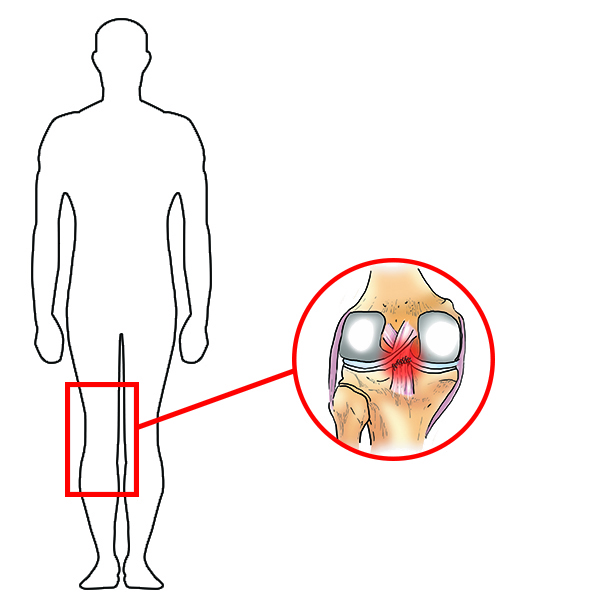

USZKODZENIE WIĘZADŁA KRZYŻOWEGO TYLNEGO (PCL)

Więzadło krzyżowe tylne (PCL) to solidne pasmo tkankowe, łączące kość udową z piszczelą, które jest znacznie mocniejsze niż ACL. Wraz z więzadłem krzyżowym przednim (ACL) zabezpieczają dolną część kości udowej i górną część kości piszczelowej, co pozwala na utrzymanie tych dwóch kości wspólnie i formowanie stawu kolanowego. Więzadła krzyżowe stawu kolanowego pozwalają nam żyć aktywnie: skakać, pływać czy biegać. Problem polega na tym, że podczas tych aktywności więzadła krzyżowe oraz okoliczne tkanki miękkie mogą zostać łatwo uszkodzone. Wraz z uszkodzeniem PCL bardzo często dochodzi do zerwania innych więzadeł kolana, a także do uszkodzenia chrząstki stawowej czy łąkotki.

Uraz najczęściej występuje w wyniku wymuszonego tylnego przemieszczenia piszczeli. Do rozerwania PCL jest konieczna duża siła, dlatego bardzo często przyczyną urazu są wypadki samochodowe, gdzie dochodzi do uderzenia kolanem o deskę rozdzielczą.

Więzadła krzyżowe stawu kolanowego pozwalają nam żyć aktywnie: skakać, pływać czy biegać. Problem polega na tym, że podczas tych aktywności więzadła krzyżowe oraz okoliczne tkanki miękkie mogą zostać łatwo uszkodzone. Wraz z uszkodzeniem PCL bardzo często dochodzi do zerwania innych więzadeł kolana, a także do uszkodzenia chrząstki stawowej czy łąkotki.